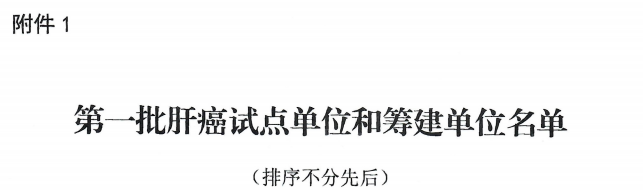

近日,国家癌症中心发布了《关于印发第一批肝癌规范诊疗质量控制试点中心名单及有关工作要求的通知》,国家癌症中心、国家肿瘤质控中心肝癌质控专家委员会在全国遴选出第一批肝癌规范诊疗质量控制试点单位(含试点筹建),我院凭借强劲综合学科实力、规范化的诊疗技术、先进的诊疗设备等优势条件通过了层层筛选,获批全国第一批肝癌规范诊疗质量控制试点单位,成为桂中区域唯一的入选医院。

据悉,肝癌规范诊疗质量控制试点单位(含试点筹建)目前广西获批仅6家,这是我院目前继乳腺癌、卵巢癌规范诊疗质量控制试点单位后又新增一个试点病种,是我院肝癌综合诊治实力和学术地位获得国家癌症中心、国家肿瘤质控中心等国家层面肯定的体现,更是对我院肿瘤规范化诊疗整体实力的肯定。